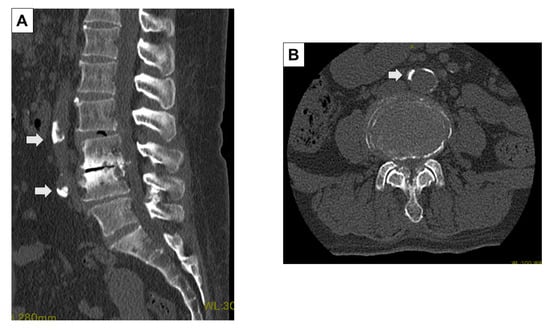

Figure 2.

Evaluation of calcification using preoperative CT images. The presence of aortic calcification, and the bifurcation level to the common iliac artery were evaluated in the preoperative CT sagittal (A) and axial images (B).